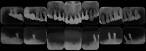

テーマは、重傷化歯周病への治療である。

歯科の疾患は、虫歯と歯周病がほぼ9割です。めがねザルも、卒業したてのときどこまで歯の保存が出来るのか、この重傷化歯周病には、頭を悩ます日々だったのです。